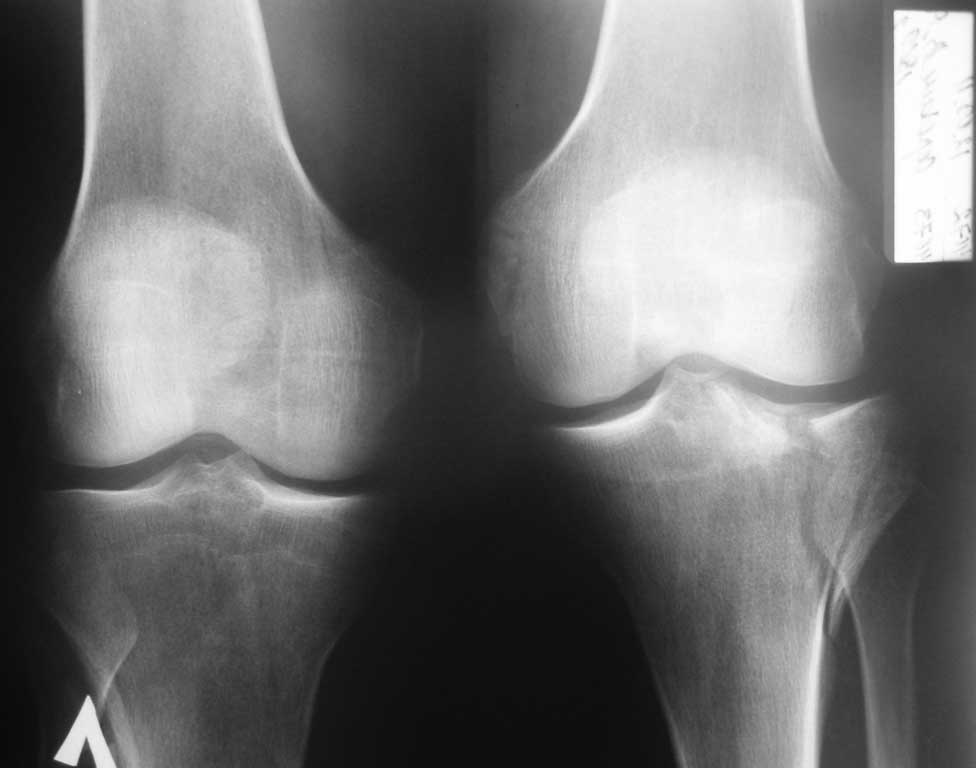

с данным переломом, в условиях отсутствия артроскопии и "Т" и "L"-образных пластин. Травма в результате ДТП, 41 год, пост геморрагическая анемия, перелом тибиального плато, В1. Имеются в наличии только спонгиозные шурупы ( смешно конечно и горько). Хотелось бы уточнить, стоит ли делать артротомию для репозиции, или попытаться закрыто фиксировать перелом?

Надо начать с уточнения характера перелома, т.е. с КТ. Похоже, там есть участки импрессии.

Здравствуйте! Я бы для начала выполни бы КТ исследование данного перелома? Почему? Потому что за таким, якобы простым переломом может скрываться импрессия части тибиального плато, которая остается незамеченной при обычных рентгенснимках. Не надо быть самоуверенным, при принятии решения о способах лечения при якобы явном характере перелома после выполнения обычных рентгенснимках, особенно при внутрисуставных переломах. По моему, после выполнения КТ, и если имеется импрессия тибиального плато, выполнить артротомию, произвести открытую репозицию перелома с устранением импрессии и фиксацией винтами перелома 3,5 мм винтами , при этом можно использовать шайбы под головки винтом. Почему винты 3,5 мм, потому что они лучше сохраняют костную ткань, чем винты 6,5 мм. С помощью нескольких 3,5 мм винтом можно создать армированный каркас для удержания тибиального плато от вторичного проседания.

Существует разработанная программа диагностики, хирургической техники лечения мыщелковых переломов.В данном случае это split- depression type и показана репозиция,фиксация поддерживающей пластиной, костная пластика.